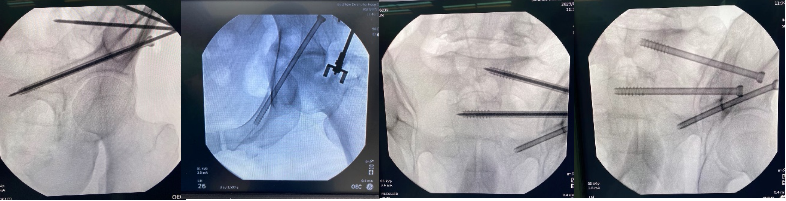

手术当天,骨科治疗组组长何罕亮副主任医师带领团队采用先进的二代臂机对患者进行骨盆图像采集,并将影像学资料上传至机器人计算机中。经过机器人的精密运算,患者的骨折三维图像非常直观地呈现在医生面前。随后,何主任团队根据图像实时进行手术规划,选择最佳置钉通道。手术机器人机械臂根据制定好的路线精准定位,将误差控制在1mm之内,使得医生不必扩大切口即可暴露骨折断端。只需3个毫米级切口,螺钉便可精准打入狭长的耻骨中,避免损伤重要的血管、神经组织。通道确定后,整个置钉过程短短几分钟便完成了,手术出血量不足10ml。精准的置钉操作使得医生不必担心反复调整所致的钉道松动,术后透视也进一步确认了螺钉位置准确无误,这预示着手术圆满成功。

机器人术中规划髋臼前柱螺钉&骨盆骶髂螺钉